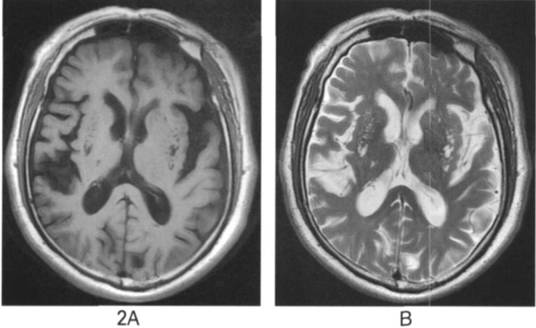

A.横断位T1WI显示双侧基底节多发斑点状低信号灶;B.T2WI显示高信号C.FLAIR成像显示为脑脊液信号,其周围脑组织信号正常D.DWI显示无弥散受限